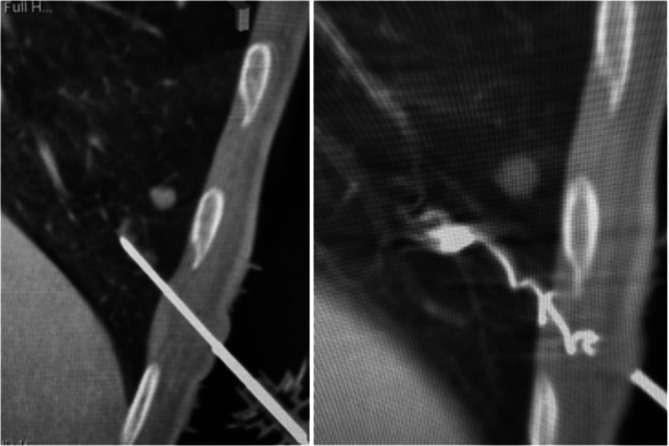

Methods: We retrospectively analyzed data from 13 patients with single, small, peripheral, non-subpleural GGOs or SSN. All patients underwent successful microcoil localization using CB-CT guidance followed by uniportal VATS resection. A microcoil was positioned partly in the lung parenchyma and partly in the extra-pleural space to assist in intraoperative localization. We evaluated the rate of correct microcoil placement and the technical success of the resection.

Results: Microcoil placement was successfully performed in all patients, with an average procedure time of 28.8 ± 10.8 min. The mean nodule size was 9.9 ± 5.4 mm, and 76.9% of the nodules were classified as ground-glass opacities. No intraparenchymal bleeding was observed, and four patients (30.8%) experienced pneumothorax, all of which were self-limited and required no intervention or coil repositioning. The uniVATS resection success rate was 100%.

Conclusion: CBCT-guided microcoil localization, with partial placement of the coil in the extra-pleural space, proved to be a highly effective technique for the localization and resection of small pulmonary nodules. The procedure demonstrated high accuracy, minimal complications, reduction of procedural time, and short hospital stays. Intraoperative fluoroscopy was never necessary, with a high reduction in radiation exposure for the patient and the operator. Further studies with larger populations and longer follow-ups are needed to validate these findings.